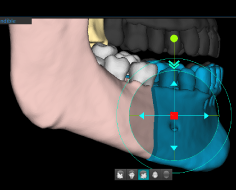

Приятным бонусом к ортодонтическим возможностям сегментации является виртуальное удаление зубов при планировании операции имплантации.

Функция виртуального удаления зубов

Планируемое место имплантации

Подбор имплантата и визуализация размещения